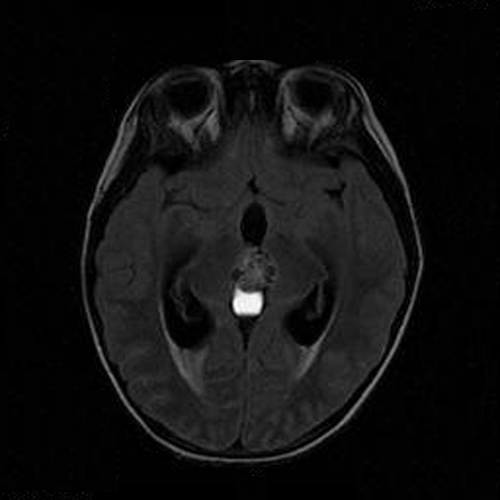

The patient was a 5 year-old Vietnamese boy who presented with the chief complaints of headaches, vomiting, and ataxia.  CT scan revealed a pineal tumor with small calcifications and hydrocephalus (Panel 1).  On MRI, the mass is a well demarcated midline mass involving the pineal area. There is also heterogeneous enhancement and cystic component (Panel 2 and 3).

FLAIR